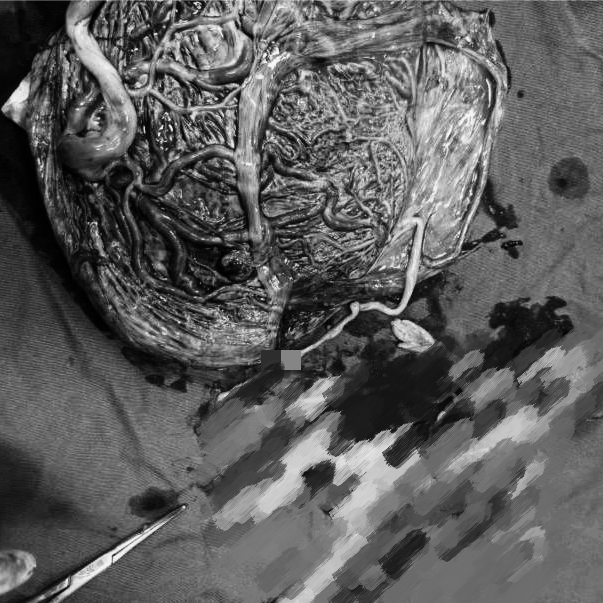

多年来,贵州航天医院各科室紧跟医学前沿,不断强技术、补短板,大力开展新技术、新项目,完成了许多高精尖、高难度、本地区“首例”的技术,填补了医院医疗技术空白,满足了群众日益增长的医疗需求。 复杂性双胎超声监护耗时耗力,技术难度大,风险高,为填补本地区复杂性双胎的超声监护技术空白,我院超声科在遵义市率先开展了此项技术,有效满足了双胎孕妇产检需求,保障了双胎新生儿的平安健康。 本期,我们将为大家带来超声科特色技术——复杂性双胎的超声监护。 案例分享 案例一 28岁的孕妇,自然受孕,怀有单绒毛膜双羊膜囊双胎(MCDA),在我院定期产检的过程中,孕32周超声检查发现两个胎儿的大脑中动脉血流流速(MCA-PSV)相差>0.7倍数的正常值(MoM),高度怀疑发生了双胎贫血红细胞增多序列征(TAPS)。为进一步明确诊断,产科立即组织超声科、手术室、新生儿科等科室进行多学科会诊(MDT),诊断为:双胎贫血红细胞增多序列征(TAPS),在征得孕妇及其家属的同意后,决定提前分娩,及时保障了两名胎儿的生命和健康。 双胎大脑中动脉血流 双胎贫血红细胞增多序列征(TAPS) 案例二 一名26岁的孕妇,是完全双角子宫,且为左侧子宫妊娠,怀有单绒毛膜双羊膜囊双胎(MCDA),一直在我院规律产检,孕16周时,超声检查发现双胎生长不一致,体重相差超过25%,考虑子宫畸形合并早发选择性胎儿宫内生长受限。孕妇在咨询相关上级医院专家后,得到减胎的建议,又前来我院咨询,在我院超声科和产科的合作下,查阅了大量文献、认真评估检查报告后,建议孕妇继续双胎妊娠。在规律、严密的超声监护下,双胎除体重差异外未出现严重胎儿并发症,在34周进行了分娩,截至目前,新生儿生长发育均正常。 胎儿生长曲线及子宫畸形三维重建 出生时体重差异 十月龄时 案例三 一名30岁的孕妇,自然受孕,怀有单绒毛膜双羊膜囊双胎(MCDA),在孕22周时超声检查发现双胎发生了选择性胎儿宫内生长受限,遂转诊到上级医院拟行胎儿镜治疗,但在行治疗的前一天,较小的胎儿在宫内发生死亡,在充分与孕妇及家属沟通后,要求继续妊娠,在定期规范的产检下,严密监测胎儿生长发育及胎儿颅脑MRI影像,最终在孕37周时通过剖宫产分娩,目前新生儿生长发育情况良好。 双胎之一胎死宫内(右图) 贵州航天医院自2021年开展复杂性双胎的超声监护以来,已服务大量双胎孕妇,集齐了所有单绒毛膜双羊膜囊双胎(MCDA)并发症病例,由经验丰富的超声医师进行此项检查,产科专业团队进行双胎的规范化监护和分娩,并与重庆医科大学附属第一医院建立了转诊通道,能够及时获得该院专家的指导和支持,为广大孕产妇提供优质、全面的医疗保障。 点击跳转贵州航天医院便民服务电话 什么是复杂性双胎的超声监护 “双胎”被称为产科之王,单绒毛膜双胎则为王中王,主要是因为单绒毛膜双羊膜囊双胎(MCDA)两胎儿共用一个胎盘,胎盘中存在血管吻合。 双胎妊娠的产前筛查及诊断主要依靠超声,相对于单胎妊娠,双胎妊娠并不是单胎检查的重复,双胎妊娠尤其是复杂性双胎的超声诊断更为重要的是关注双胎间循环的关联,双胎间生理及病理改变的相互影响,双胎间血流动力学监测及双胎间差异比较。 超声如何诊断 复杂性双胎并发症 在孕14周以前,超声要明确双胎的绒毛膜性:是单绒毛膜(MC)还是双绒毛膜(DC);孕10周前,可以通过孕囊的个数确定绒毛膜性;孕11周—14周,可以通过胎儿的性别、双胎之间隔膜的厚度、双胎儿分隔膜处胎盘的形态等来区分绒毛膜性。 双绒毛膜双胎的管理和单胎差不多,基本不需要增加超声检查的频次。单绒毛膜的管理相对谨慎,按照国际国内指南规范,单绒毛膜双胎自第16周起,每两周对双胎儿进行生长发育评估及血流检查。 复杂性双胎的超声监护,对超声医生技术要求较高,孕早期需对双胎的绒毛膜性进行精确判断;产科医生根据绒毛膜性制定孕期的产检计划;超声医生掌握胎儿宫内情况,及时与产科医生沟通,精确了解胎儿宫内安危后制定合适的治疗方案,给出适当的终止妊娠时机;复杂性双胎一般都面临早产的风险,所以新生儿团队的专业保障不可或缺,降低新生儿出生后的并发症及提高新生儿生活质量。复杂性双胎的较好妊娠结局,是通过孕期超声科、产科紧密合作,及新生儿出生后新生儿科管理多学科团队合作所获得的。 贵州航天医院超声科专家团队 吴艳辉 超声科 学科带头人 主任医师 专业擅长:从事超声诊断工作约30年,对心血管、小器官超声、超声引导下介入等具有丰富的临床经验。 骆科美 超声科 副主任医师 专业擅长:从事超声诊断工作33年,对胎儿心脏及颅脑、妇产超声诊断、盆底超声等诊断具有丰富的临床经验。 胡大海 超声科 副主任医师 专业擅长:从事超声工作17年,对心血管、外周血管、浅表器官超声诊断等具有丰富的临床经验。 刘 敏 超声科 副主任医师 专业擅长:从事超声诊断工作20余年,对妇产科超声、心脏血管超声诊断具有丰富的临床经验。 贵州航天医院超声科简介 贵州航天医院超声科配备多种超声检查设备(飞利浦彩超(IU-22、IU-Elite、HD11、Q5、Q7),迈瑞超声I9、DC-6、DC-8、GE-E8及床旁机,彩色超声诊断仪等),设有心血管诊室、妇产科诊室、腹部诊室、绿色通道、浅表小器官等检查室。 • ✦ 专科特色 ✦ • 四肢血管超声检查、双胎产前筛查及超声监护、超声造影检查技术、介入超声临床应用、经颅脑实质超声辅助筛查诊断帕金森病、女性性早熟超声诊断、盆底超声检查等。 NT超声检查 超声介入引导 肝脏超声造影 甲状腺造影 颅脑超声帕金森辅助检查 乳腺超声造影 上肢动静脉造瘘超声检查 双胎超声筛查 下肢血管超声检查 右心造影 • ✦ 诊疗范围 ✦ • 科室业务覆盖腹部、泌尿、妇科、产科(常规、NT筛查、III级筛查超声检查及高危妊娠监护)、成人心脏、外周血管、浅表器官(包含甲状腺、乳腺、阴囊、眼睛等)、颅脑(小儿颅脑、成人颅脑)、小儿肺超、造影、盆底、腹直肌、肌骨神经等检查及各种介入引导。